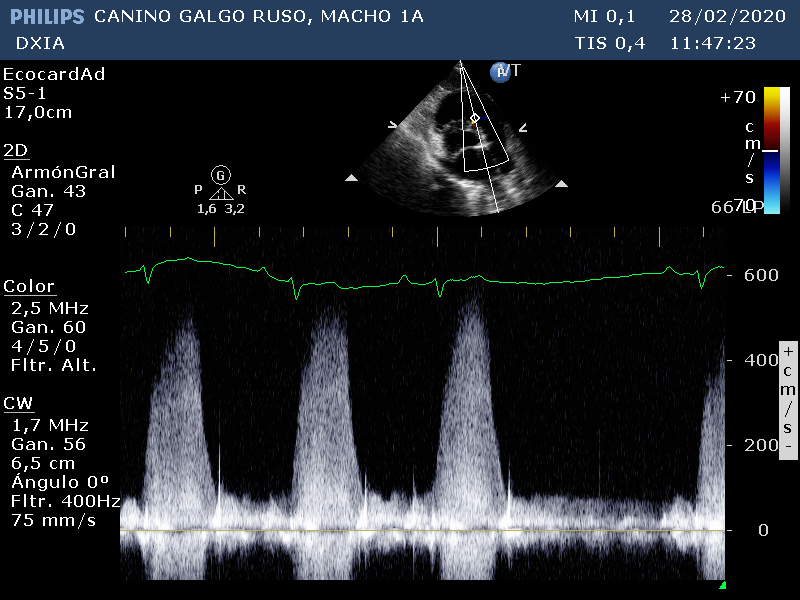

Medición del flujo turbulento del defecto del septo IV (imagen 1)

Medición del flujo turbulento del defecto del septo IV (imagen 2)